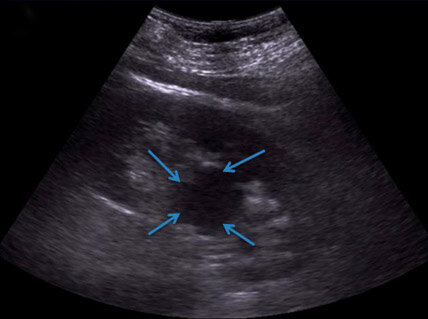

УЗИ почек. Обнаруживает округлое образование, которое локализуется в паренхиме органа или экстраренально.